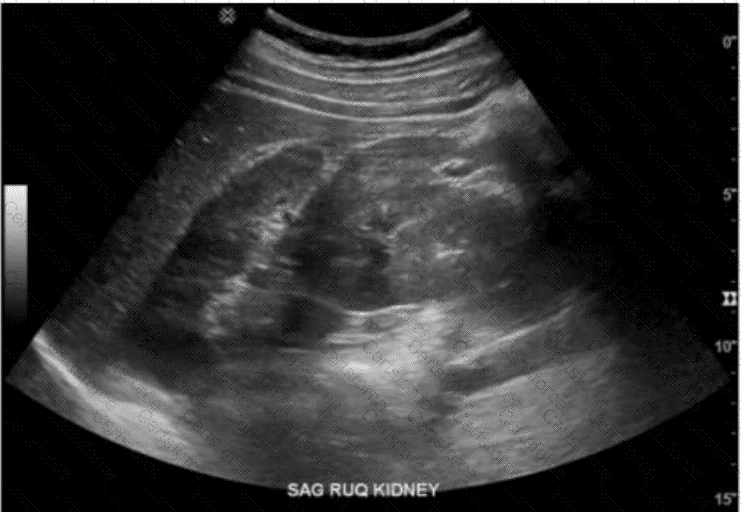

The ultrasound image labeled “SAG RUQ KIDNEY” demonstrates a midline sagittal view showing a renal parenchymal structure that extends across the midline anterior to the aorta and vertebral bodies, suggesting the presence of a horseshoe kidney.

A horseshoe kidney is a congenital renal anomaly in which the lower poles of both kidneys are fused across the midline by a parenchymal or fibrous isthmus. This isthmus typically lies anterior to the aorta and inferior vena cava and can be seen as a hypoechoic band of tissue crossing the midline on ultrasound.

Ultrasound findings characteristic of a horseshoe kidney:

Abnormally low position of the kidneys in the abdomen

Renal tissue (isthmus) bridging the lower poles anterior to the great vessels

Renal axes may be more horizontal than usual

Kidneys may appear closer together or “kissing” the spine anteriorly